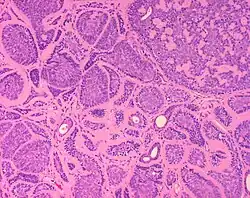

Dermal cylindromas are:

- Dermal lesions consisting of nests of cells that are surrounded by hyaline (i.e., glassy, eosinophilic, acellular) material and have:

- Hyperchromatic nuclei that may palisade (columnar nuclei arranged around the periphery of the cell nests with their short axis tangential to the nest periphery), and

- Cells with lighter staining ovoid nuclei at their centre.

They lack of a significant number of lymphocytes; this differentiates them from spiradenomas.

Micrograph of a dermal cylindroma in H&E stain. -